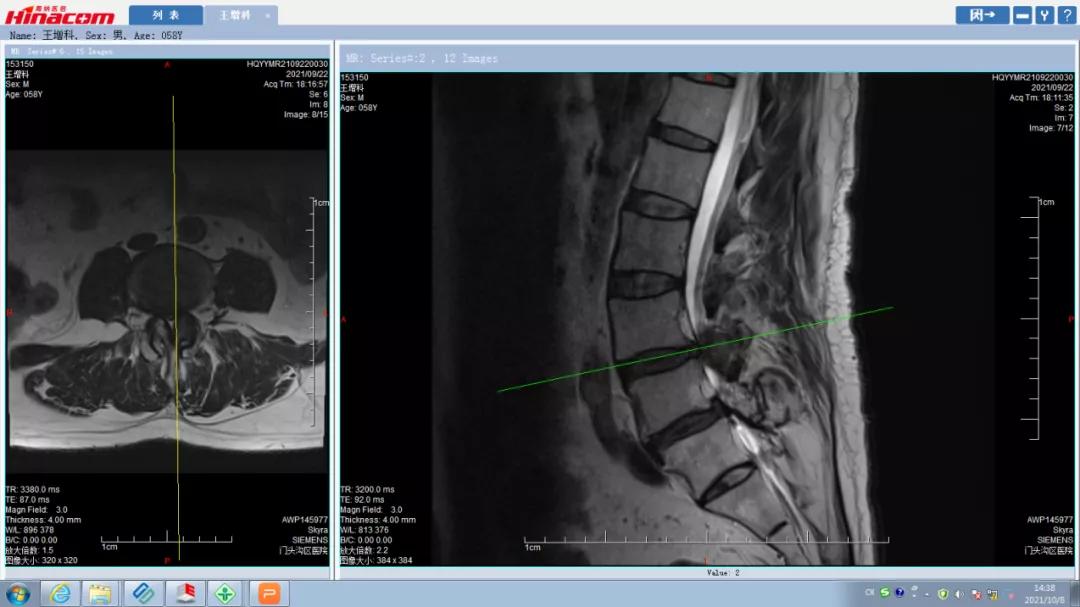

腰椎管矢状面--术前MRI

腰45椎管水平面--术前MRI

正常腰椎管水平面--术前MRI